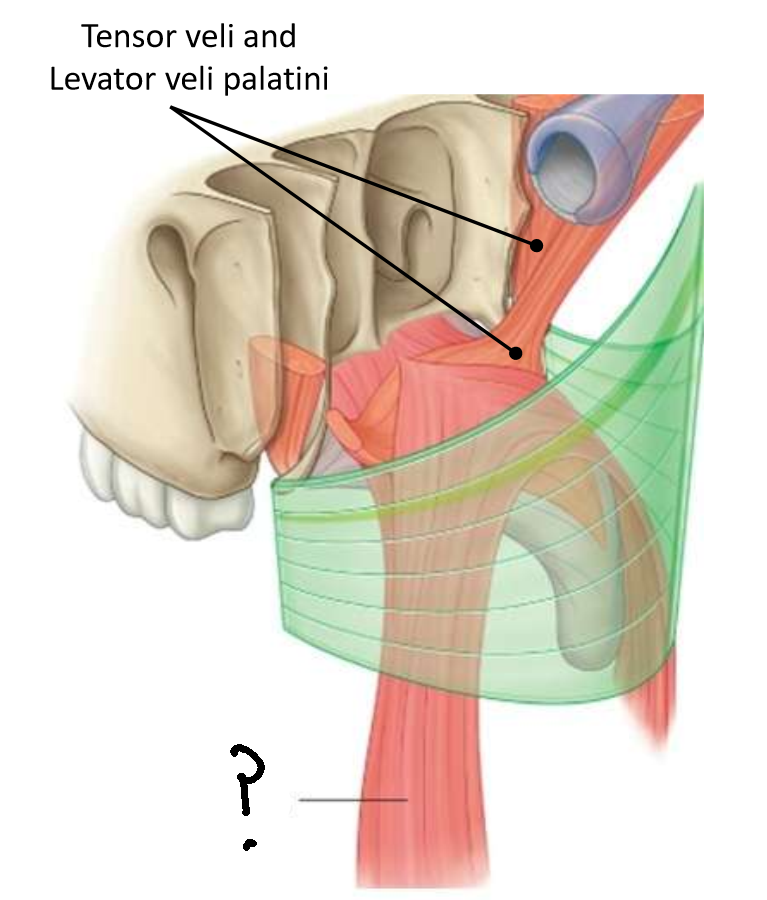

Which muscle is this?

tensor veli palatini

What are the two parts of this muscle?

muscular and fibrous

What is the function of this muscle?

tenses soft palate, opens pharyngotympanic tube

What innervates this muscle?

medial pterygoid nerve of mandibular branch of trigeminal

Which muscle is this?

levator veli palatini

What are the attachments of this muscle?

petrous part of temporal bone and pharyngotympanic tube → palatine aponeurosis

What is the function of this muscle?

lifts soft palate to close nasopharyngeal isthmus

What innervates this muscle?

pharyngeal branch of pharyngeal plexus of vagus nerve